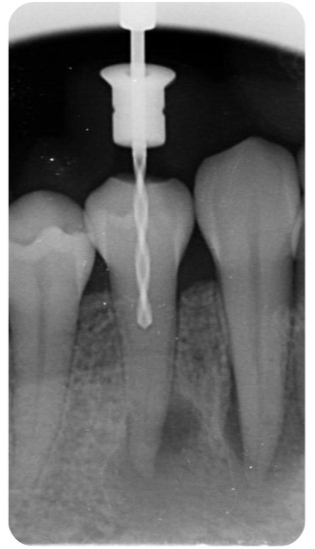

💻 2.PLANIFICACIÓN VIRTUAL

Comunicación por llamada o chat con nuestros odontólogos para finalizar la planificación.